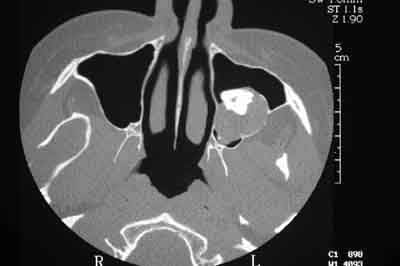

Femme de 40 ans. Aucun antécédent (notamment chirurgical) en dehors d'un DNID, d'un tabagisme modéré (5 paquets-année) et d'une surcharge pondérale. Consulte pour apparition progressive d'une volumineuse voussure dans les 2 vestibles inférieurs et d'une modification consécutive de la forme de la partie inférieure de son visage. A l'examen clinique : tuméfaction dure et fixée dans les 2 vestibules. Sensibilité (V3) normale. Gencive normale. Dents restantes non mobiles, vitales. Pas d'adénopathies palpables. Biologie non faite pour l'instant. Je vous joinds l'OTP et le scan. Diagnostic et options de traitement?

Bref, en ce qui concerne ce cas (assez récent), je vous livre le raisonnement qui a été le notre : probables kystes péricoronnaires sur les dents incluses (il n'y a pas de dents "surnuméraires"...). Décision d'abord chirurgical pour énucléation des 3 kystes (les ponctions ne "marchent" pas dans ces lésions) et examens anatomopathologiques extemporanés pour décider, en per-opératoire, de la conduite à tenir (photo 1).

Diagnotic extemporané : kératokystes (!). Les dents incluses se sont donc avérées être un piège diagnostic! Le traitement s'est de ce fait contenté d'un curetage appuyé des paroies osseuses, conservation des 2 nerfs dentaires et, en raison de la taille des kystes mandibulaires et du risque de fracture post-opératoire, nous avons y avons associé une greffe (hydroxyapatite + os autologue (crête illiaque) + PRP) au niveau mandibulaire uniquement (photos 2 et 3)et blocage intremaxillaire pendant 15 jours.